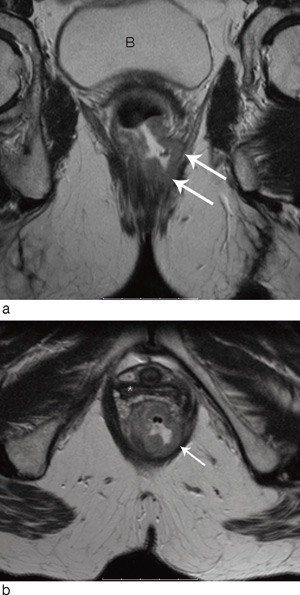

MR

Evalueringen av status for kirurgisk reseksjonsrand blir svært nøyaktig med MR (4, 19, 21, 24 – 27). Reproduserbarheten ble nylig også evaluert i en stor multisenterstudie. 679 pasienter ved 11 europeiske sentre ble undersøkt, og 311 av disse ble primæroperert. Resultatene viste 92 % nøyaktighet i evalueringen av om kirurgisk reseksjonsrand var involvert eller truet (tumor innen 1 mm fra fascien) (28) (fig 5). Man undersøkte i denne studien også hvor nøyaktig MR kunne fastslå tumors dybdeinfiltrasjon i mesorectum utenfor muscularis propria (29). Den gjennomsnittlige forskjellen mellom infiltrasjonsdybden målt med MR og dybden målt ved histopatologisk analyse var – 0,05 mm.

Glandelevaluering

Glandelutredning er vanskelig – uansett hvilken av de tilgjengelige metoder man bruker. I den tradisjonelle CT-evalueringen har man bare gått ut fra glandelstørrelsen. Dette har vist seg lite nøyaktig i evaluering av spredning fra rectumcancer, hvor mange metastatiske glandler er under 5 mm i diameter (34). Man har derfor forsøkt å finne andre kriterier enn størrelse som korrelerer bedre med histopatologisk status (35).

Brown og medarbeidere sammenliknet høyoppløselig MR-undersøkelse og histopatologisk undersøkelse på glandel-til-glandel-basis hos 42 pasienter med rectumcancer (34). Ved evaluering av veggkonturene samt homogenitet av glandlene oppnådde de en sensitivitet på 85 % og en spesifisitet på 98 % i vurderingen av om en glandel på > 3 mm var malign eller ikke. Koh og medarbeidere har gjort en MR-studie for å evaluere bruken av USPIO-kontrast (ultrasmall particles of iron oxide) ved kolorektale metastaser (36). Dette er spesielle jernholdige kontrastmidler som akkumuleres i normale lymfeknuter, men ikke i maligne. Resultatet var svært lovende. Kontrastmidlet er imidlertid ennå ikke kommersielt tilgjengelig, og flere og større studier er nødvendig. Heller ikke PET-CT har vist tilfredsstillende resultater når det gjelder glandelevaluering. Heriot og medarbeidere fant bare 29 % sensitivitet for positive glandler (37).